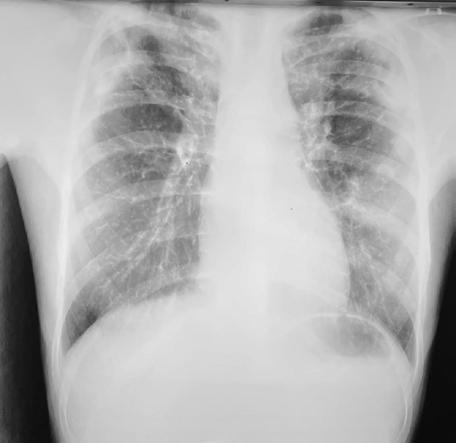

Eosinophilia and Pulmonary infiltrates as a first sign of Primary Hypereosinophilic Syndrome in a 13,5 years old girl

Ανάλογα με τον απόλυτο αριθμό των ηωσινοφίλων, χαρακτηρίζεται ως ήπια, μέτρια ή σοβαρή. Παρουσιάζεται η περίπτωση κοριτσιού 13.5 ετών, που προσκομίστηκε με πυρετό, αίσθημα κόπωσης, βήχα, κοιλιακό άλγος και σοβαρού βαθμού ηωσινοφιλία και πνευμονικά διηθήματα. Επιχειρείται βήμα - βήμα η διαγνωστική προσπέλαση του περιστατικού, παρατίθεται ο

λεπτομερής εργαστηριακός και παρακλινικός έλεγχος, η πορεία της νόσου μέχρι να τεθεί η τελική διάγνωση, αυτή του Ιδιοπαθούς Υπερηωσινοφιλικού Συνδρόμου, καθώς και η θεραπευτική της αντιμετώπιση.

Λέξεις-κλειδιά: ηωσινοφιλία, πνευμονικά διηθήματα, ιδιοπαθές υπερηωσινοφιλικό